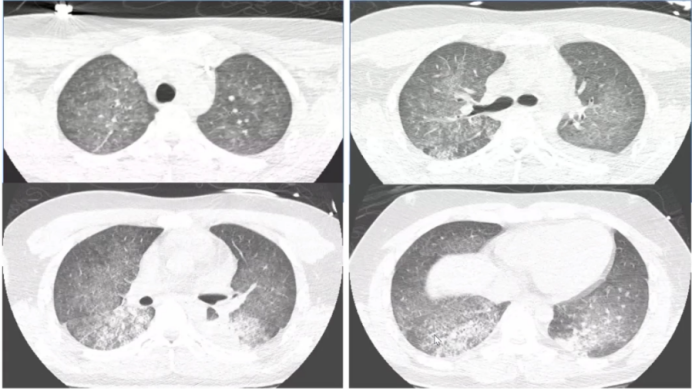

相较于GPA,显微镜下多血管炎(MPA)的影像变化更加多样[6,7]如下图所示,MPA患者胸部CT可见细网格影,也可能出现如同机化性肺炎样实变,甚至有支气管扩张,还有患者会出现胸膜受累表现。

图片